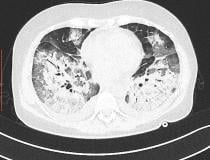

This photo gallery shows the variety of radiological presentations of COVID-19 (SARS-CoV-2) in medical imaging, including computed tomography (CT), radiograph X-rays, ultrasound, echocardiograms and magnetic resonance imaging (MRI). The radiology images show examples of typical COVID pneumonia in the lungs and the numerous complications the virus causes in the body in multiple organs, including the brain, kidneys, heart, abdomen and vascular system.